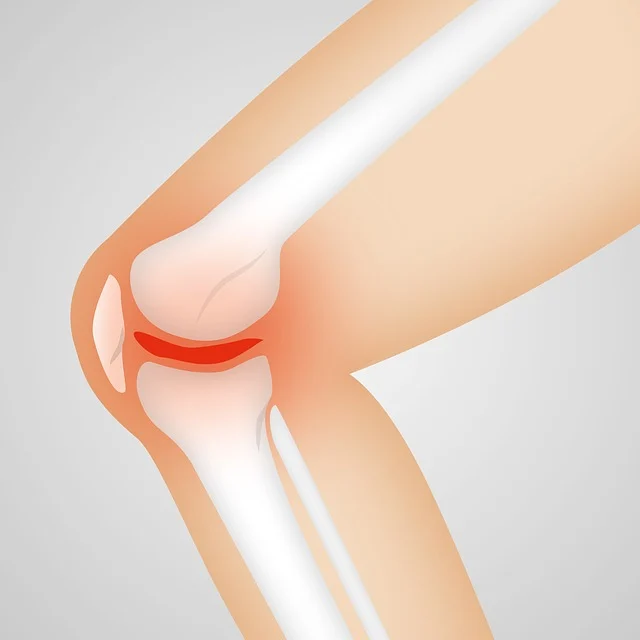

- 콜라겐(특히 2형 콜라겐)

- 연골의 주성분으로, 연골 건강 유지와 관절 탄력성을 높이는 데 기여합니다.

- 닭연골에서 추출한 2형 콜라겐이 가장 효과적입니다.

- 히알루론산

- 관절액(윤활액)의 주요 성분으로, 무릎 관절의 마찰을 줄이고 부드럽게 움직이도록 돕습니다.

- 연골 보호 및 통증 완화 효과가 있습니다.